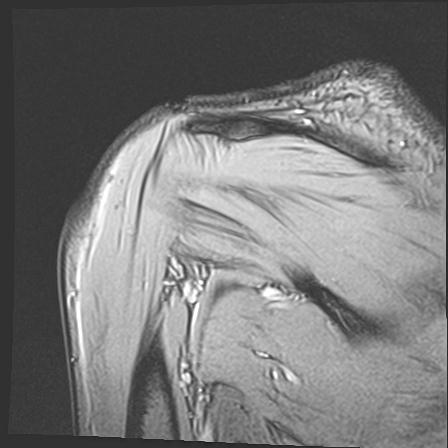

60058 3/9 11/4 右肩 2R+MRI 73歳男性 肩腱板損傷